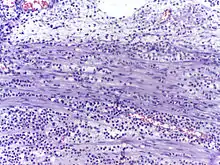

![]() Neutrophils with segmented nuclei surrounded by erythrocytes and platelets. Intra-cellular granules are visible in the cytoplasm (Giemsa stained). | |